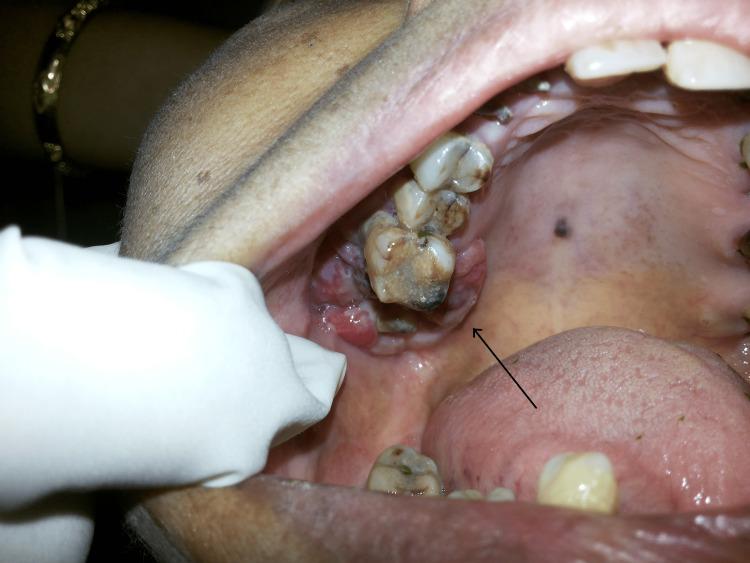

Melanoma of the oral cavity is a rare malignant tumor that develops from a malignant melanocytic or de novo from melanocytes within the normal mucosa or skin and appears blue, black, or reddish-brown. Oral mucosal melanoma has a higher proclivity for metastasis and attacks tissue more aggressively than any other malignant tumor in the mouth. Intestinal melanoma of the head and neck is an uncommon type of cancer that should be counted among the deadliest. Malignant melanoma of the oral cavity accounts for only 0.2%-8.0% of all reported melanoma, although accounting for 1.3% of all malignancies. Because most melanotic mucosal lesions are painless at first, the diagnosis is sometimes delayed until the ulcer or growth causes symptoms. Early detection is critical for effective therapy and the only way to improve survival and prognosis in patients with oral malignant melanoma due to its poor prognosis. To avoid oral melanomas, every single colored lesion identified in the oral cavity should be treated with suspicion and adequate inquiry because a colored lesion might expand, and it should be referred for a biopsy to avoid poisoning. This article shows how the oral clinic is important in the diagnosis of oral ulcers and argues that early detection is necessary to enhance patient outcomes.

口腔黑色素瘤是一种罕见的恶性肿瘤,它由恶性黑素细胞发展而来,或者起源于正常黏膜或皮肤内的黑素细胞,表现为蓝色、黑色或红棕色。口腔黏膜黑色素瘤比口腔内的任何其他恶性肿瘤更易发生转移,侵袭组织的能力更强。头颈部肠道黑色素瘤是一种罕见的癌症类型,属于最致命的癌症之一。口腔恶性黑色素瘤仅占所有报告黑色素瘤的0.2%-8.0%,尽管占所有恶性肿瘤的1.3%。由于大多数黑色素性黏膜病变起初无痛,诊断有时会延迟,直到溃疡或肿物引起症状。早期检测对于有效治疗至关重要,由于口腔恶性黑色素瘤预后较差,这也是改善患者生存和预后的唯一途径。为避免口腔黑色素瘤,口腔内发现的每一个有色病变都应受到怀疑并进行充分询问,因为有色病变可能会扩大,应转诊进行活检以避免误诊。本文展示了口腔诊所在口腔溃疡诊断中的重要性,并认为早期检测对于改善患者预后是必要的。